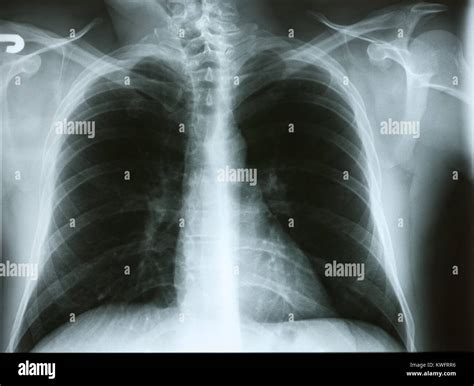

Mucus, or phlegm, is produced by the mucous membranes lining your respiratory tract. Under normal circumstances, it is thin and watery, helping to keep your airways moist and trapping dust or allergens. However, when you become ill or are exposed to environmental triggers, your body ramps up production to fight off invaders. When this mucus becomes too thick or is produced in large quantities, it becomes difficult for your cilia—the tiny, hair-like structures in your lungs—to move it out, resulting in that dreaded mucus in chest sensation.

Common contributors to chest congestion include:

• Viral Infections: The common cold, flu, and bronchitis are the most frequent culprits.

• Bacterial Infections: Pneumonia often causes thick, discolored mucus.

• Allergies: Inhaling pollen, pet dander, or dust mites can trigger inflammation and excess mucus.

• Environmental Irritants: Smoke, pollution, and strong chemical fumes can irritate the lining of the lungs.

• Asthma or COPD: Chronic conditions that cause the airways to narrow and produce more mucus than usual.